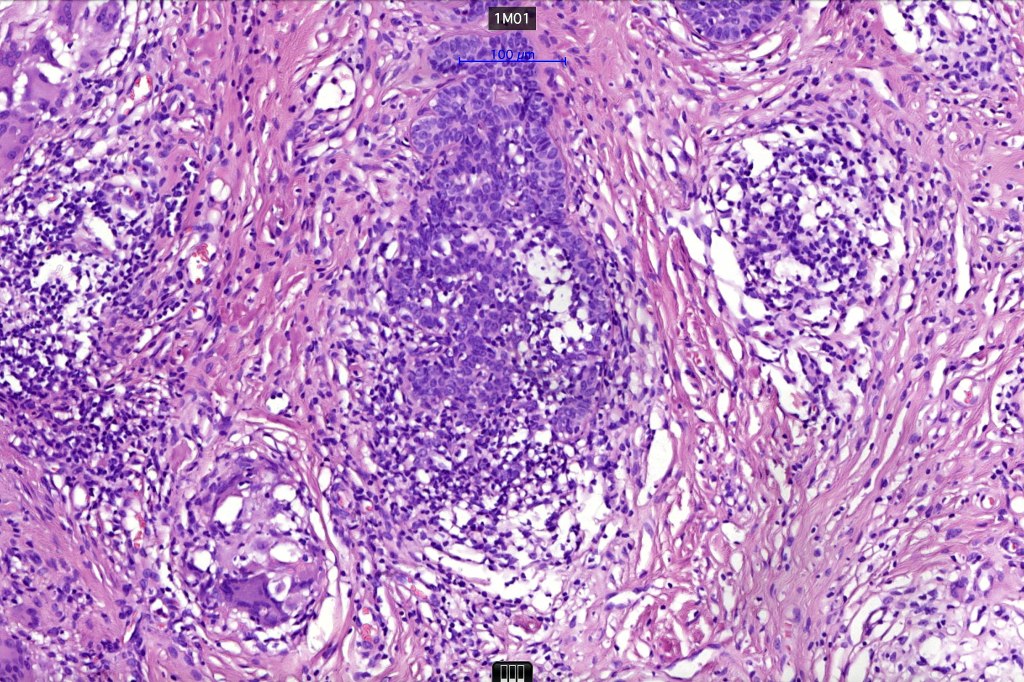

Histological features

•The classical appearance consists of keratocysts & lobules of basaloid cells

•Some tumors are devoid of keratocysts

•Variable continuity with the epidermis

•Basaloid lobules show peripheral palisading

•Retraction artifact and mucin deposition as seen in BCC are not present

•Mitoses & apoptosis may be present

•Perifollicular mesenchyme is always conspicuous and sometimes densely aggregated are seen indenting the baslaloid lobules (papillary mesenchymal bodies)

•Narrow epithelial strands arising from the basaloid lobules are often present

•Amyloid, foreign body granuloma formation to free keratin & calcification are variable features

Trichoepithelioma should be distinguished from trichoblastoma since the latter is very rarely syndromic. Trichoepithelioma is largely a dermal tumor whereas trichoblastoma often extends from the dermis into subcutaneous fat or deeper in very large examples. Papillary mesenchymal bodies are much better formed and generally more obvious in trichoepithelioma. Trichoepithelioma must also be distinguished from basal cell carcinoma. Retraction artifact & stromal mucin are features of basal cell carcinoma and not trichoepithelioma. Papillary mesenchymal bodies are not seen in basal cell carcinoma.